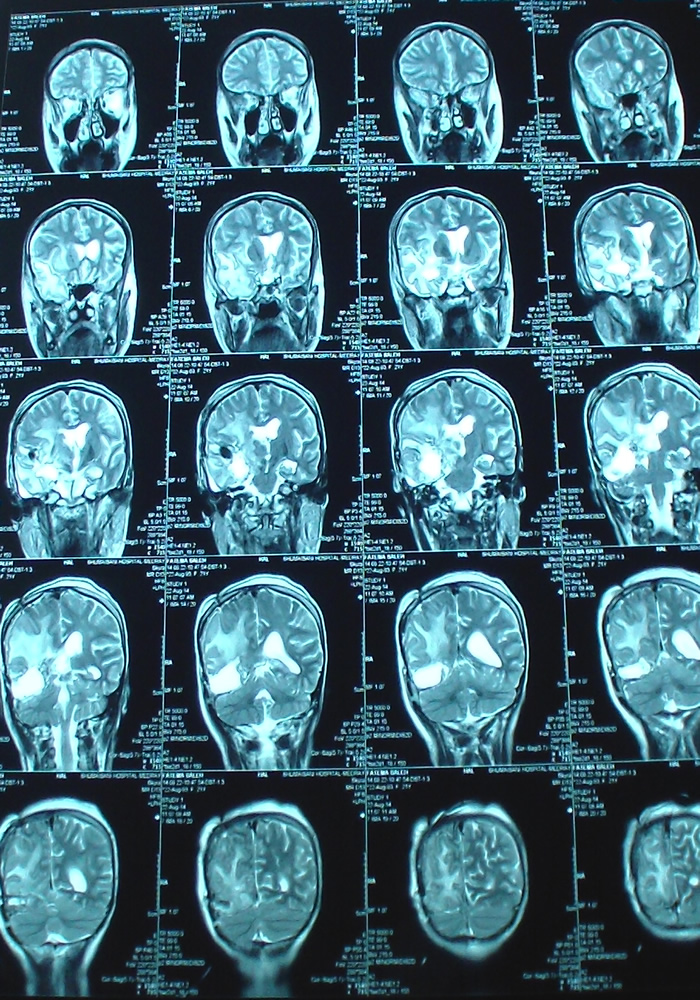

Axial TW2 done the second postoperative day.

Coronal MRI done the next postoperative day. Notice how near the dissection to the right internal capsule.

Sagittal TW1  done the next postoperative day. Notice the radical resection, in comparison to the MRI done during surgery.

Spectroscopy done the next postoperative day, showing the absence of tumor and the chemical shift of the internal capsule, which was seen during surgery and it was respected. This is the first time in my life seeing the internal capsule during surgical dissection.